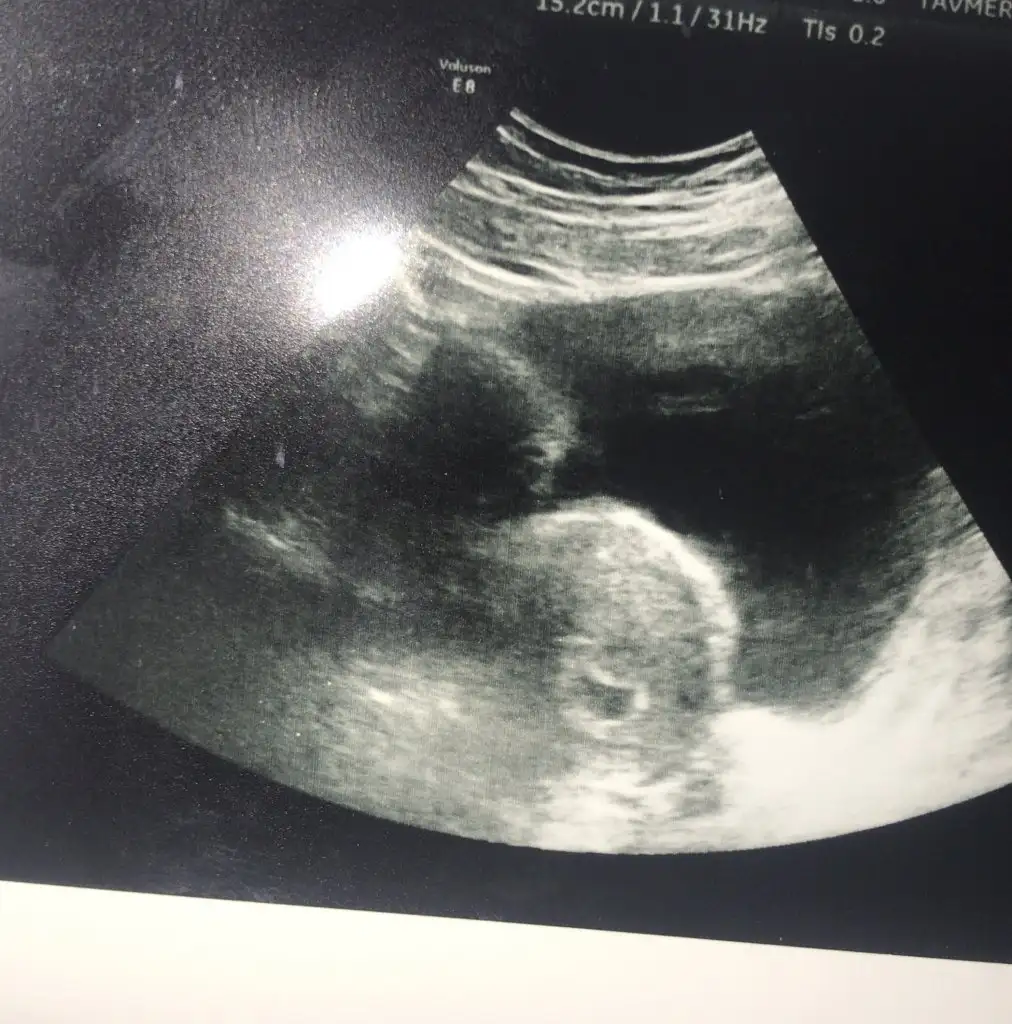

YaaaaaaaEki Görüntüle 2821409

Kesemi gordum sukurler olsun :))